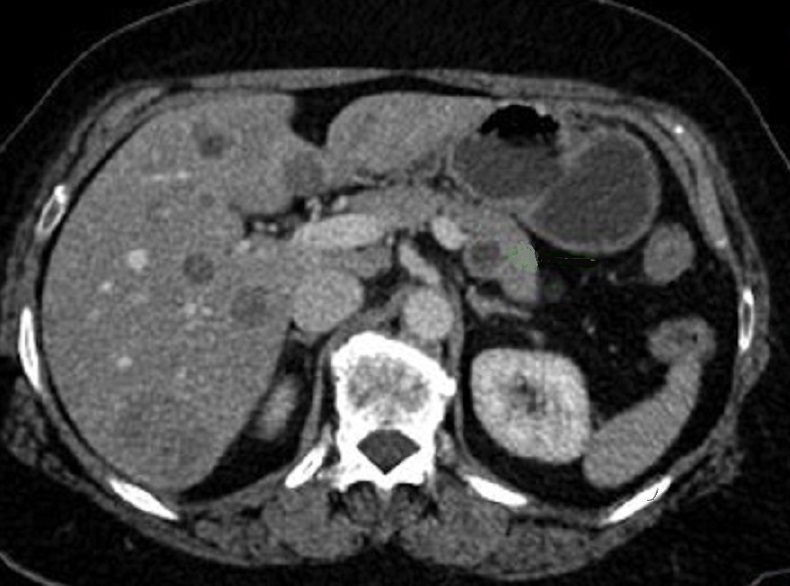

Image radiologique des metastase en

aspect lesionaire hypodense du foie droit ( fleche

rouge ) . Ce sont des nodule metastasique a distance

au foie droit . Image TDM en coupe axiale . |